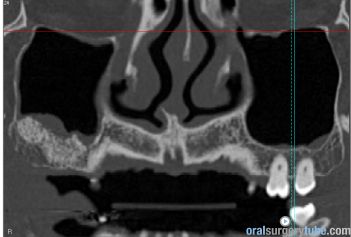

Con este comentario haremos una pausa en el caso hasta que llegue la colocación de los implantes. Por el momento, está todo solucionado. No hay sintomatología alguna, y lo más importante, en TAC realizado el martes 31.07.2018, podemos ver que el seno ha drenado por completo y está aireado. Hasta nuevo aviso, suspendemos todo tipo de medicación. Subimos imágenes del último TAC donde podemos apreciar que hemos perdido algo de xenoinjerto, pero la zona de menor altura aún tiene 10 mm. Podemos ver en una de las imágenes la zona de la ventana por donde el seno drenaba. Esperaremos el tiempo reglamentario para poder reevaluar si el xenoinjerto sigue siendo viable. Ha sido un gran placer contar con este equipo y poder aportar un grano de arena a solucionar complicaciones quirúrgicas.

Continúo con el seguimiento que vamos dando a este paciente: Visitado el miércoles 11.07.2018. Hay ausencia total de sintmatología. Retiramos el drenaje, hacemos Prueba de Valsalva positiva, pero sale aire y un poco de sangre. Dejamos cicatrizar por segunda intención. Pedimos continuar la medicación antibiótica y solicitamos un TAC. El seno maxilar está ocupado como vemos en la imagen, pero el biomaterial está contenido en la zona injertada: no existe ningún gránulo de xenoinjerto dentro del seno. La apófisis mastoidea está aireada.